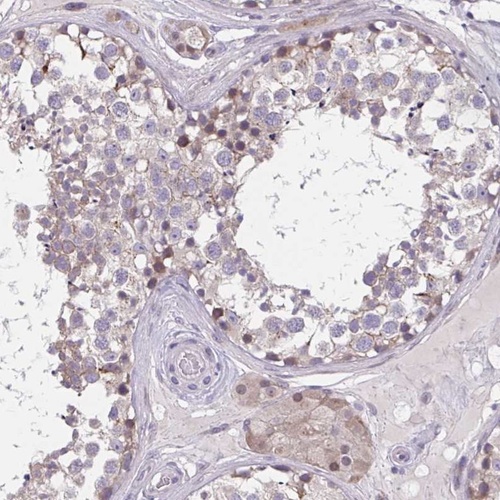

Immunohistochemistry analysis in human testis and liver tissues using Anti-CHST3 antibody. Corresponding CHST3 RNA-seq data are presented for the same tissues.